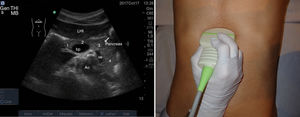

Con el transductor convexo, en epigastrio, realizaremos cortes transversales, longitudinales y oblicuos. Con la sonda en disposición transversal a nivel de epigastrio conseguimos un corte longitudinal del páncreas (fig. 9). Ventralmente o en superficie al páncreas nos encontramos con el lóbulo hepático izquierdo haciendo de ventana acústica. Dorsalmente o en profundidad con respecto al páncreas se sitúan la confluencia esplenoportal, la vena esplénica, la arteria mesentérica superior y la aorta, entre las que discurre la vena renal izquierda que desemboca en la cava.

Con la sonda en disposición longitudinal a nivel de epigastrio conseguimos un corte transversal del páncreas (fig. 10). Ventralmente o en superficie al páncreas nos encontramos con el lóbulo hepático izquierdo y el estómago con contenido líquido. Dorsalmente o en profundidad con respecto al páncreas se sitúan la arteria mesentérica superior y la aorta, entre las que discurre la vena renal izquierda.